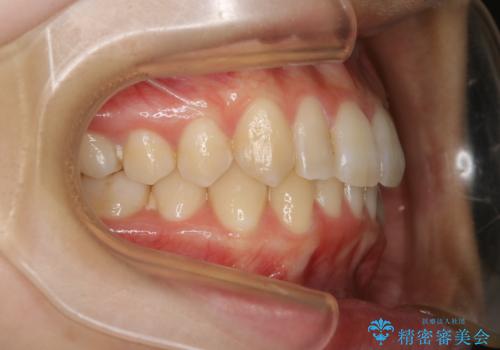

下顎前歯の先天欠損と上顎前歯のクロスバイト:インビザライン治療

- 上の前歯が1本後ろに入ってしまっていることが気になるとご相談にいらした方です。

元々下の前歯が1本欠損しており、上下の噛み合わせや、歯のサイズバランスを考慮しながら治療を行いました。

クロスバイトしている歯が深く噛み込んでおり、この歯を外に出してくる際に強い咬合力が加わると歯が失活する恐れがあることを説明し、合わせて咬筋へのボトックス注入を行いました。

下顎切歯が1本欠損しているため、上顎前歯部を少しずつストリッピングして、上下の噛み合わせ、バランスの向上を図りました。